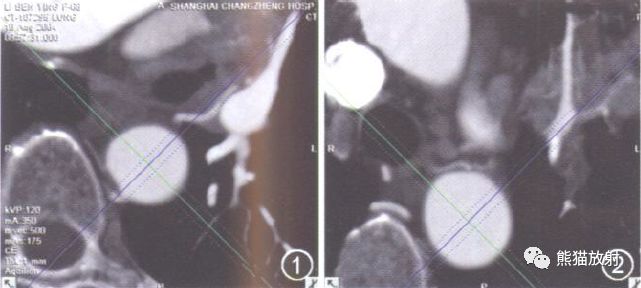

图1-4 左肺鳞癌, 中央型。原始横断面上将主动脉均分为4象限, 显示L2 起点位于Ⅱ象限即后壁(图1);L1起点位于Ⅰ象限即前壁(图2);图3为斜位MIP, 示L2从降主动脉后壁发出后绕过主动脉进入左肺门, 供血肺癌;图4为VR, 示BA 右2左2型(R2 L2), R1源自降主动脉右侧壁, R2、L1共干, 源自降主动脉前壁。